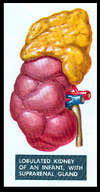

US Appearance (adults vs infants)

ADULTS

Cortex; homogeneous, slightly less than liver echogenicity

•

Medulla-Pyramids; hypoechoic compared to cortex

•

Sinus; echogenic secondary to fat and fibrous tissue

INFANTS

Cortex; more echogenic than in adults

•

Medulla-Pyramids; more prominent than adults and often mistaken for cysts

•

Sinus; not well developed and almost absent – lack of adipose tissue

how can you tell this is a pediatric kidney?

the prominence of the medullary pyramids and the lack of prominence of the renal sinus as compared to the adult kidneys. (adult below)